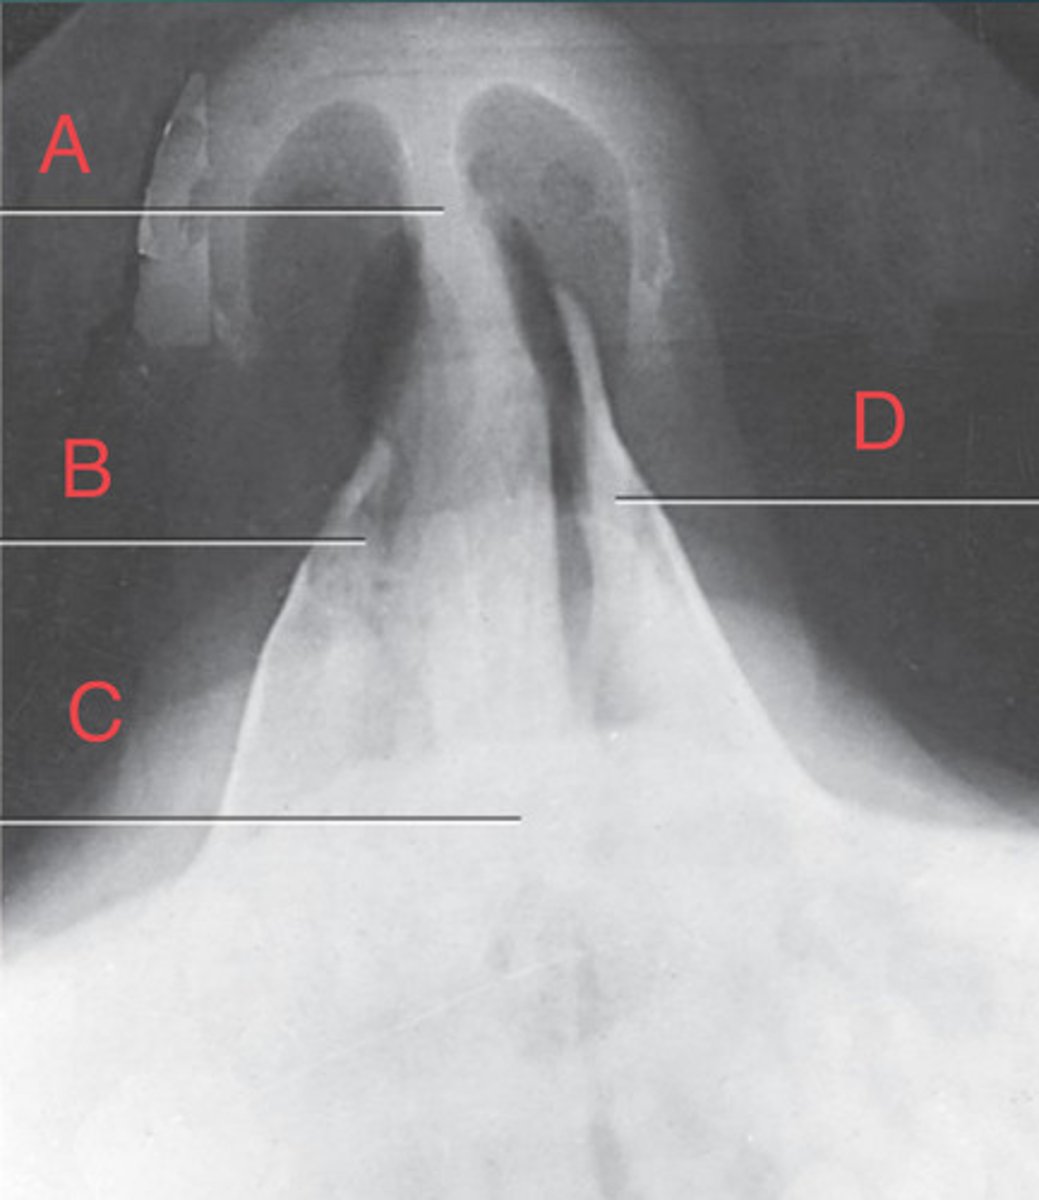

Waters sinus method

What projection?

r. frontal sinus of the frontal bone

A.

R. Maxillary sinus of maxilla

B.

R. petrous ridge of temporal bone

C.

bony nasal septum

D.

L. inferior orbital fissure of sphenoid bone

E.

Sphenoid sinus of sphenoid bone

F.

bony nasal septum

E.